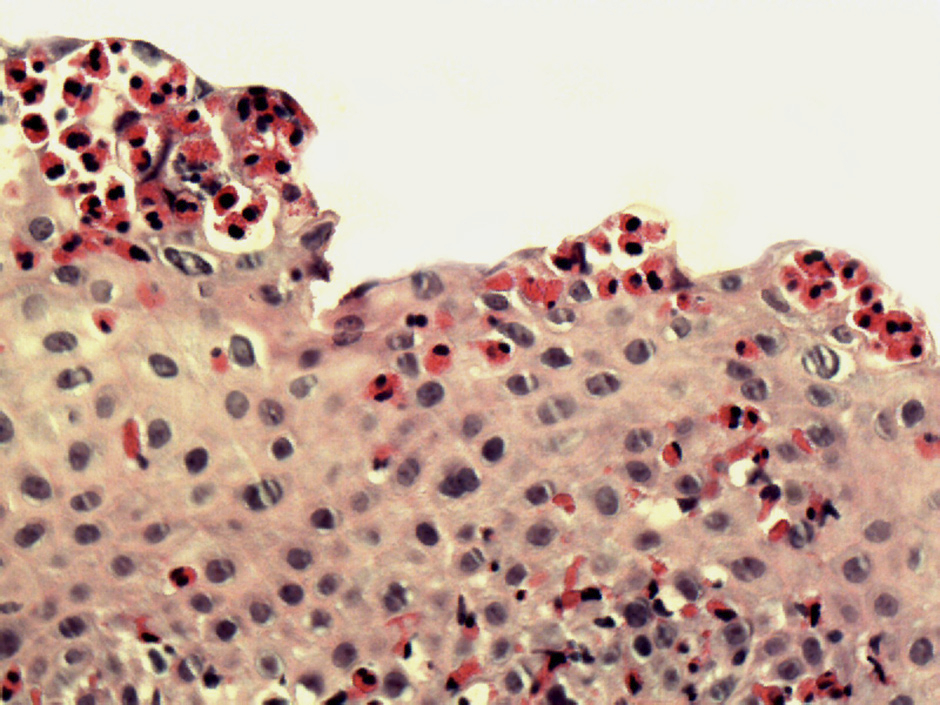

Figure 2

Biopsy specimen illustrating the leading histopathologic signs of EoE:

The histograph, taken from an adult patient with active EoE, shows a dense infiltration of the squamous esophageal epithelium with eosinophils and dilated intercellular spaces. H&E staining, original magnification x200.